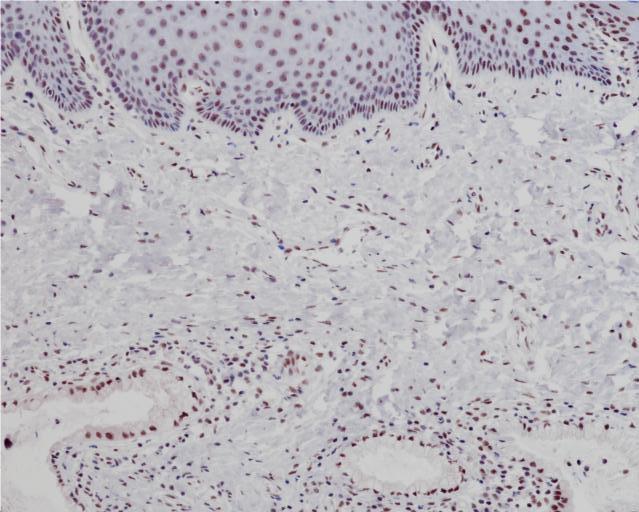

ATRX Antibody (DA273)

Diffuse gliomas are classified based on histological and molecular features to achieve an integrated diagnosis. Molecular diagnostic markers include IDH mutation, 1p/19q co-deletion, and TP53 mutation. ATRX is a chromatin remodeling protein and its mutation status may be used as a molecular diagnostic marker within the diffuse glioma classification algorithm. Anti-ATRX is used to identify mutant ATRX by a loss of ATRX expression in neoplastic cells when compared with internal positive controls (endothelial cells, glia, and neurons). Grade II/III astrocytoma classification includes IDH mutant, ATRX mutant, and 1p/19q retention, while grade II/III oligodendroglioma includes IDH mutant, ATRX wildtype, and 1p/19q co-deletion; p53 expression may also serve as an aid in diagnosis. ATRX mutation is frequently, but not always, mutually exclusive with 1p/19q co-deletion.1-6